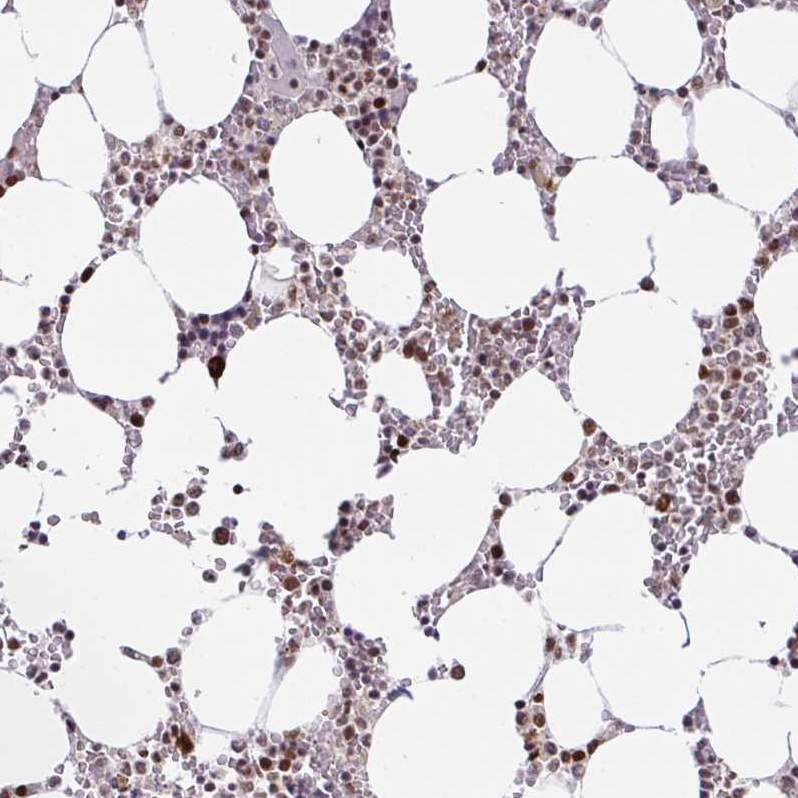

Immunohistochemical staining of human bone marrow shows strong nuclear positivity in hematopoietic cells.